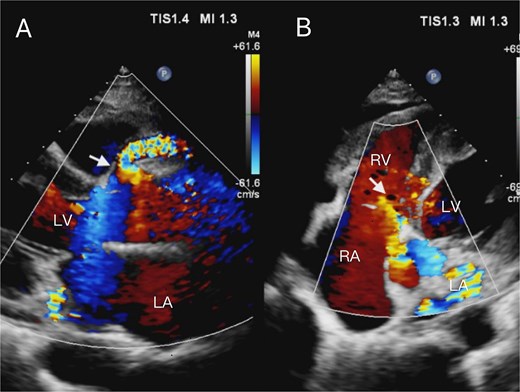

A 52-year-old woman presented to our hospital with a 2-week history of idiopathic chest tightness and chest pain. Physical examination showed systolic hypertension (140/73 mmHg). The patient had no personal or family history of cardiovascular risk factors, such as hypertension, hyperlipidemia, or diabetes mellitus. The electrocardiogram obtained at admission showed a heart rate of 80 beats per minute, normal sinus rhythm, and T-wave abnormalities. Initial laboratory evaluation revealed elevated B-type natriuretic peptide levels, while serum troponin T remained within normal limits. Routine transthoracic echocardiography revealed aneurysmal coronary artery dilation with abnormal flow trajectory (Fig. 1). Parasternal long-axis views demonstrated aneurysmal dilation of the right coronary sinus and proximal right coronary artery (Fig. 1A). Subsequent apical five-chamber views identified a fistulous orifice in the right coronary artery draining superior to the tricuspid septal leaflet into the right atrium (Fig. 1B), with a measured orifice diameter of ~5.8 mm. Subsequent coronary computed tomography angiography (CCTA) with three-dimensional reconstruction confirmed our echocardiographic findings, revealing extensive aneurysmal dilation of the right coronary artery with an RCA – RA fistula (Fig. 2A–D, Supplementary Video 1). Selective coronary angiography was performed during hospitalization, which further confirmed the presence of a giant right coronary artery aneurysm (Fig. 2E and F, Supplementary Video 2) and revealed no significant stenosis or pathology in the left coronary system. Furthermore, cardiac catheterization quantified a pulmonary-to-systemic flow ratio (Qp:Qs) of 1.8:1, indicating a moderate left-to-right shunt. Based on these findings, the patient was diagnosed with a right CAF and a giant right coronary artery aneurysm.

Transthoracic echocardiogram. (A) The parasternal long-axis view demonstrates aneurysmal dilation of the right coronary artery, with the proximal segment dilated to ~9 mm in diameter. Color Doppler echocardiography demonstrates turbulent flow within the dilated coronary artery segment(arrow). (B) The apical five-chamber view demonstrates the right atrium and right ventricle under color Doppler echocardiography. Color Doppler echocardiography reveals turbulent flow originating superior to the tricuspid septal leaflet, oriented toward the right atrium, with an associated perforation measuring ~5.8 mm in diameter (arrow).